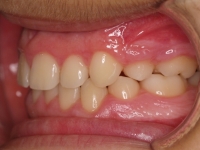

La paciente O.O. acude a nuestra consulta por:

– Canino 13 e incisivo lateral 42 en posición ectópica.

– Canino 23 incluido.

Con lo que decide realizarse un tratamiento de ortodoncia de duración de 24 meses con brackets damon Q.

CASO COMPLETO: